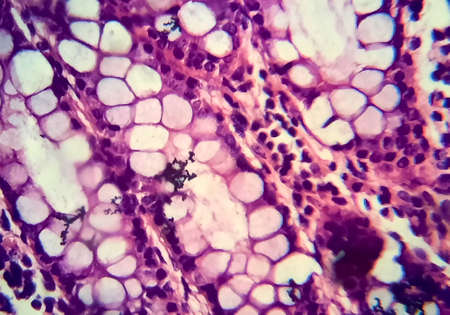

Signet ring cell carcinoma of the stomach, light micrograph, photo under microscope

Cross section of intestinal glands (crypts of Lieberkühn) showing mucous goblet cells. Human colon.

Histopathology of intestinal adenoma, light micrograph, photo under microscope

Colon carcinoma arising from adenoma, 100x

Differentiated intestinal adenocarcinoma, light micrograph, photo under microscope